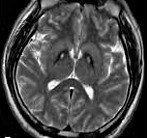

G23.0 Hallervorden-Spatz disease